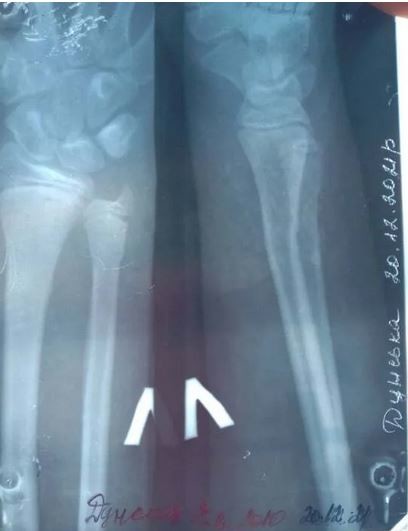

«Ми поїхали до райцентру. Нам, щоб дістатися туди, потрібно 600 грн за машину заплатити. Взяли направлення на рентген. На знімку лікар побачив подвійний перелом і доньці наклали гіпс», – розповіла мама школярки.